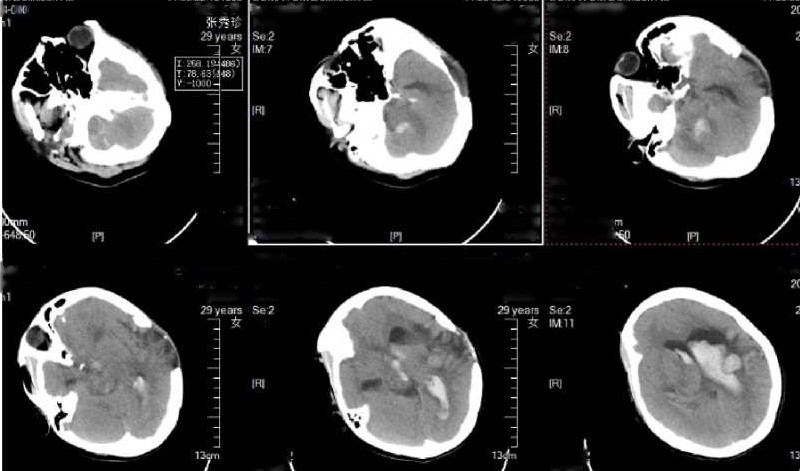

查患者浅昏迷,GCS12分,四肢肌力正常。急查头CT:显示颅内出血破入脑室。给患者行侧脑室引流术。待血肿吸收后行DSA 检查。

CT显示左侧颞叶出血破入脑室